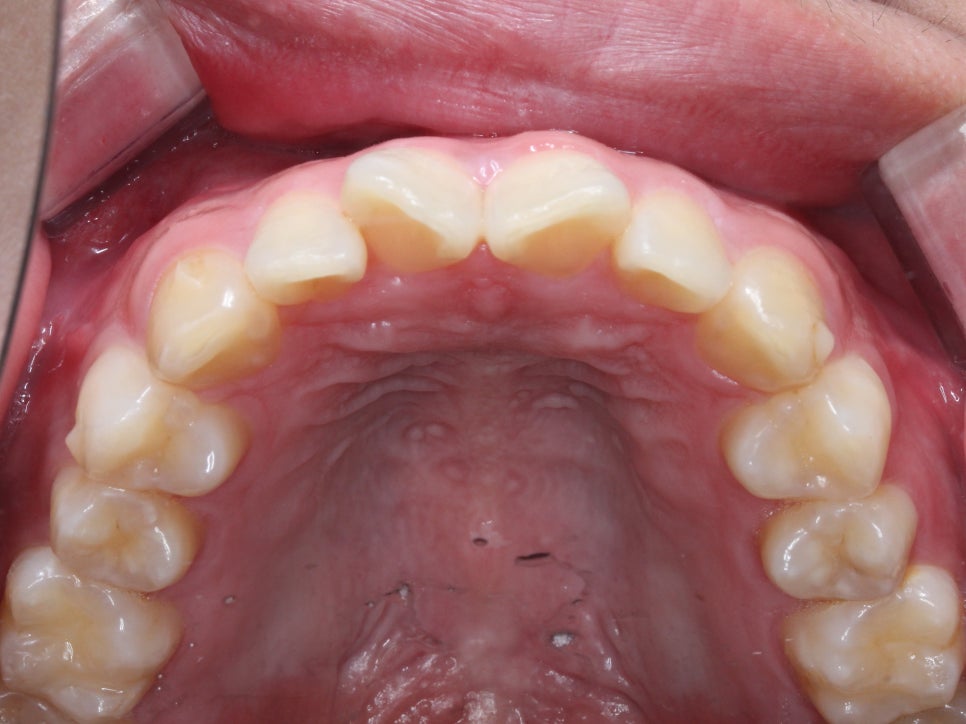

교정 전 사진을 보시면

앞니의 모양

특히 11, 12번 치아의 형태가

V자 모양으로 대칭적이게

틀어져 있는 모습입니다.

상악과 하악의 안쪽면 사진에서도

치아의 총생이 발견되었습니다.

상악의 경우 앞니의 나비치아 성향이 두드러지는 반면

하악의 경우에는 중절치의 미세한 돌출과

측절치의 이탈로 인해 총생이 발견되네요.